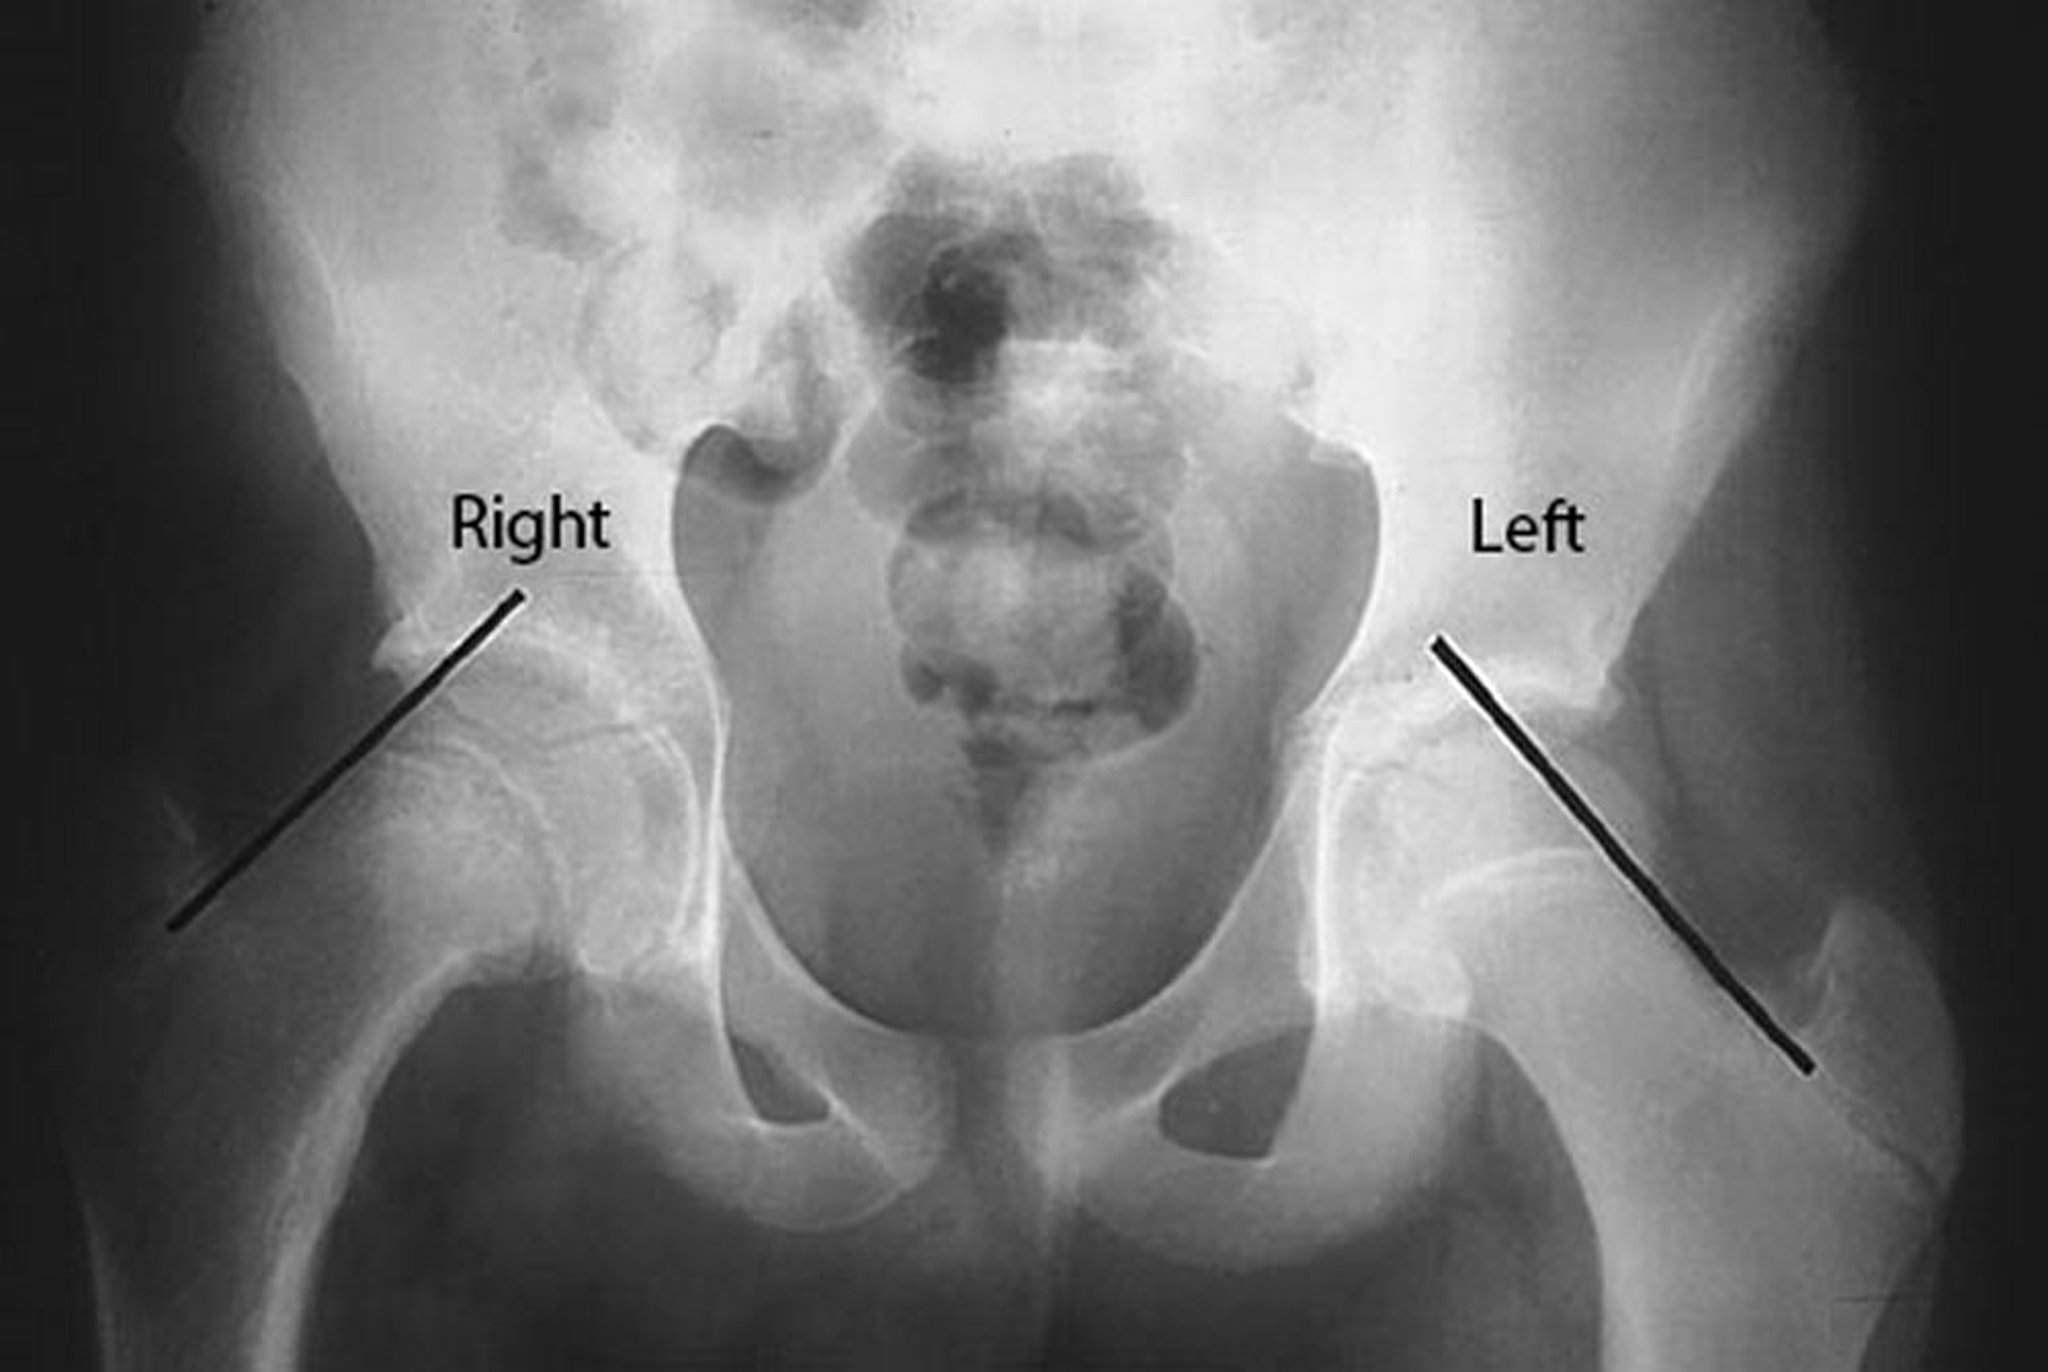

As linhas de Klein estão na borda superior do colo femoral desse paciente com DECF do lado direito do quadril. Observe que a cabeça femoral está abaixo da linha de Klein no lado direito acometido, enquanto uma parte significativa da cabeça do fêmur está acima da linha de Klein no lado esquerdo não atingido.